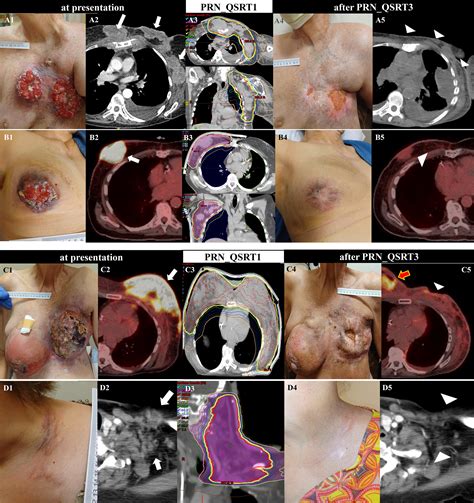

Fungating Breast Cancer

Receiving a diagnosis of fungating breast cancer is an incredibly distressing experience, often accompanied by complex physical and emotional challenges. This condition, medically referred to as malignant wound, ulcerating breast cancer, or fungating carcinoma, occurs when a tumor grows through the skin, creating an open, often non-healing wound. Understanding what this diagnosis means, how it develops, and the palliative care strategies available is essential for patients, caregivers, and families navigating this difficult journey. While the diagnosis is advanced, modern medical management focuses heavily on symptom control, comfort, and maintaining quality of life.

Fungating breast cancer is not a specific type of cancer itself, but rather a clinical presentation that can occur with various types of breast malignancy. It develops when a primary tumor or a metastatic lesion in the breast grows outward, invading the skin barrier. As the tumor increases in size, it outgrows its blood supply, leading to tissue necrosis—the death of cells—which creates the characteristic open, fungating wound.

These wounds can be deeply unsettling to look at and may be accompanied by unpleasant symptoms. However, it is vital to remember that with specialized care, these symptoms can often be managed effectively. The primary goals are to promote healing where possible, manage exudate (fluid drainage), control odor, and address pain to ensure the patient's dignity and comfort.